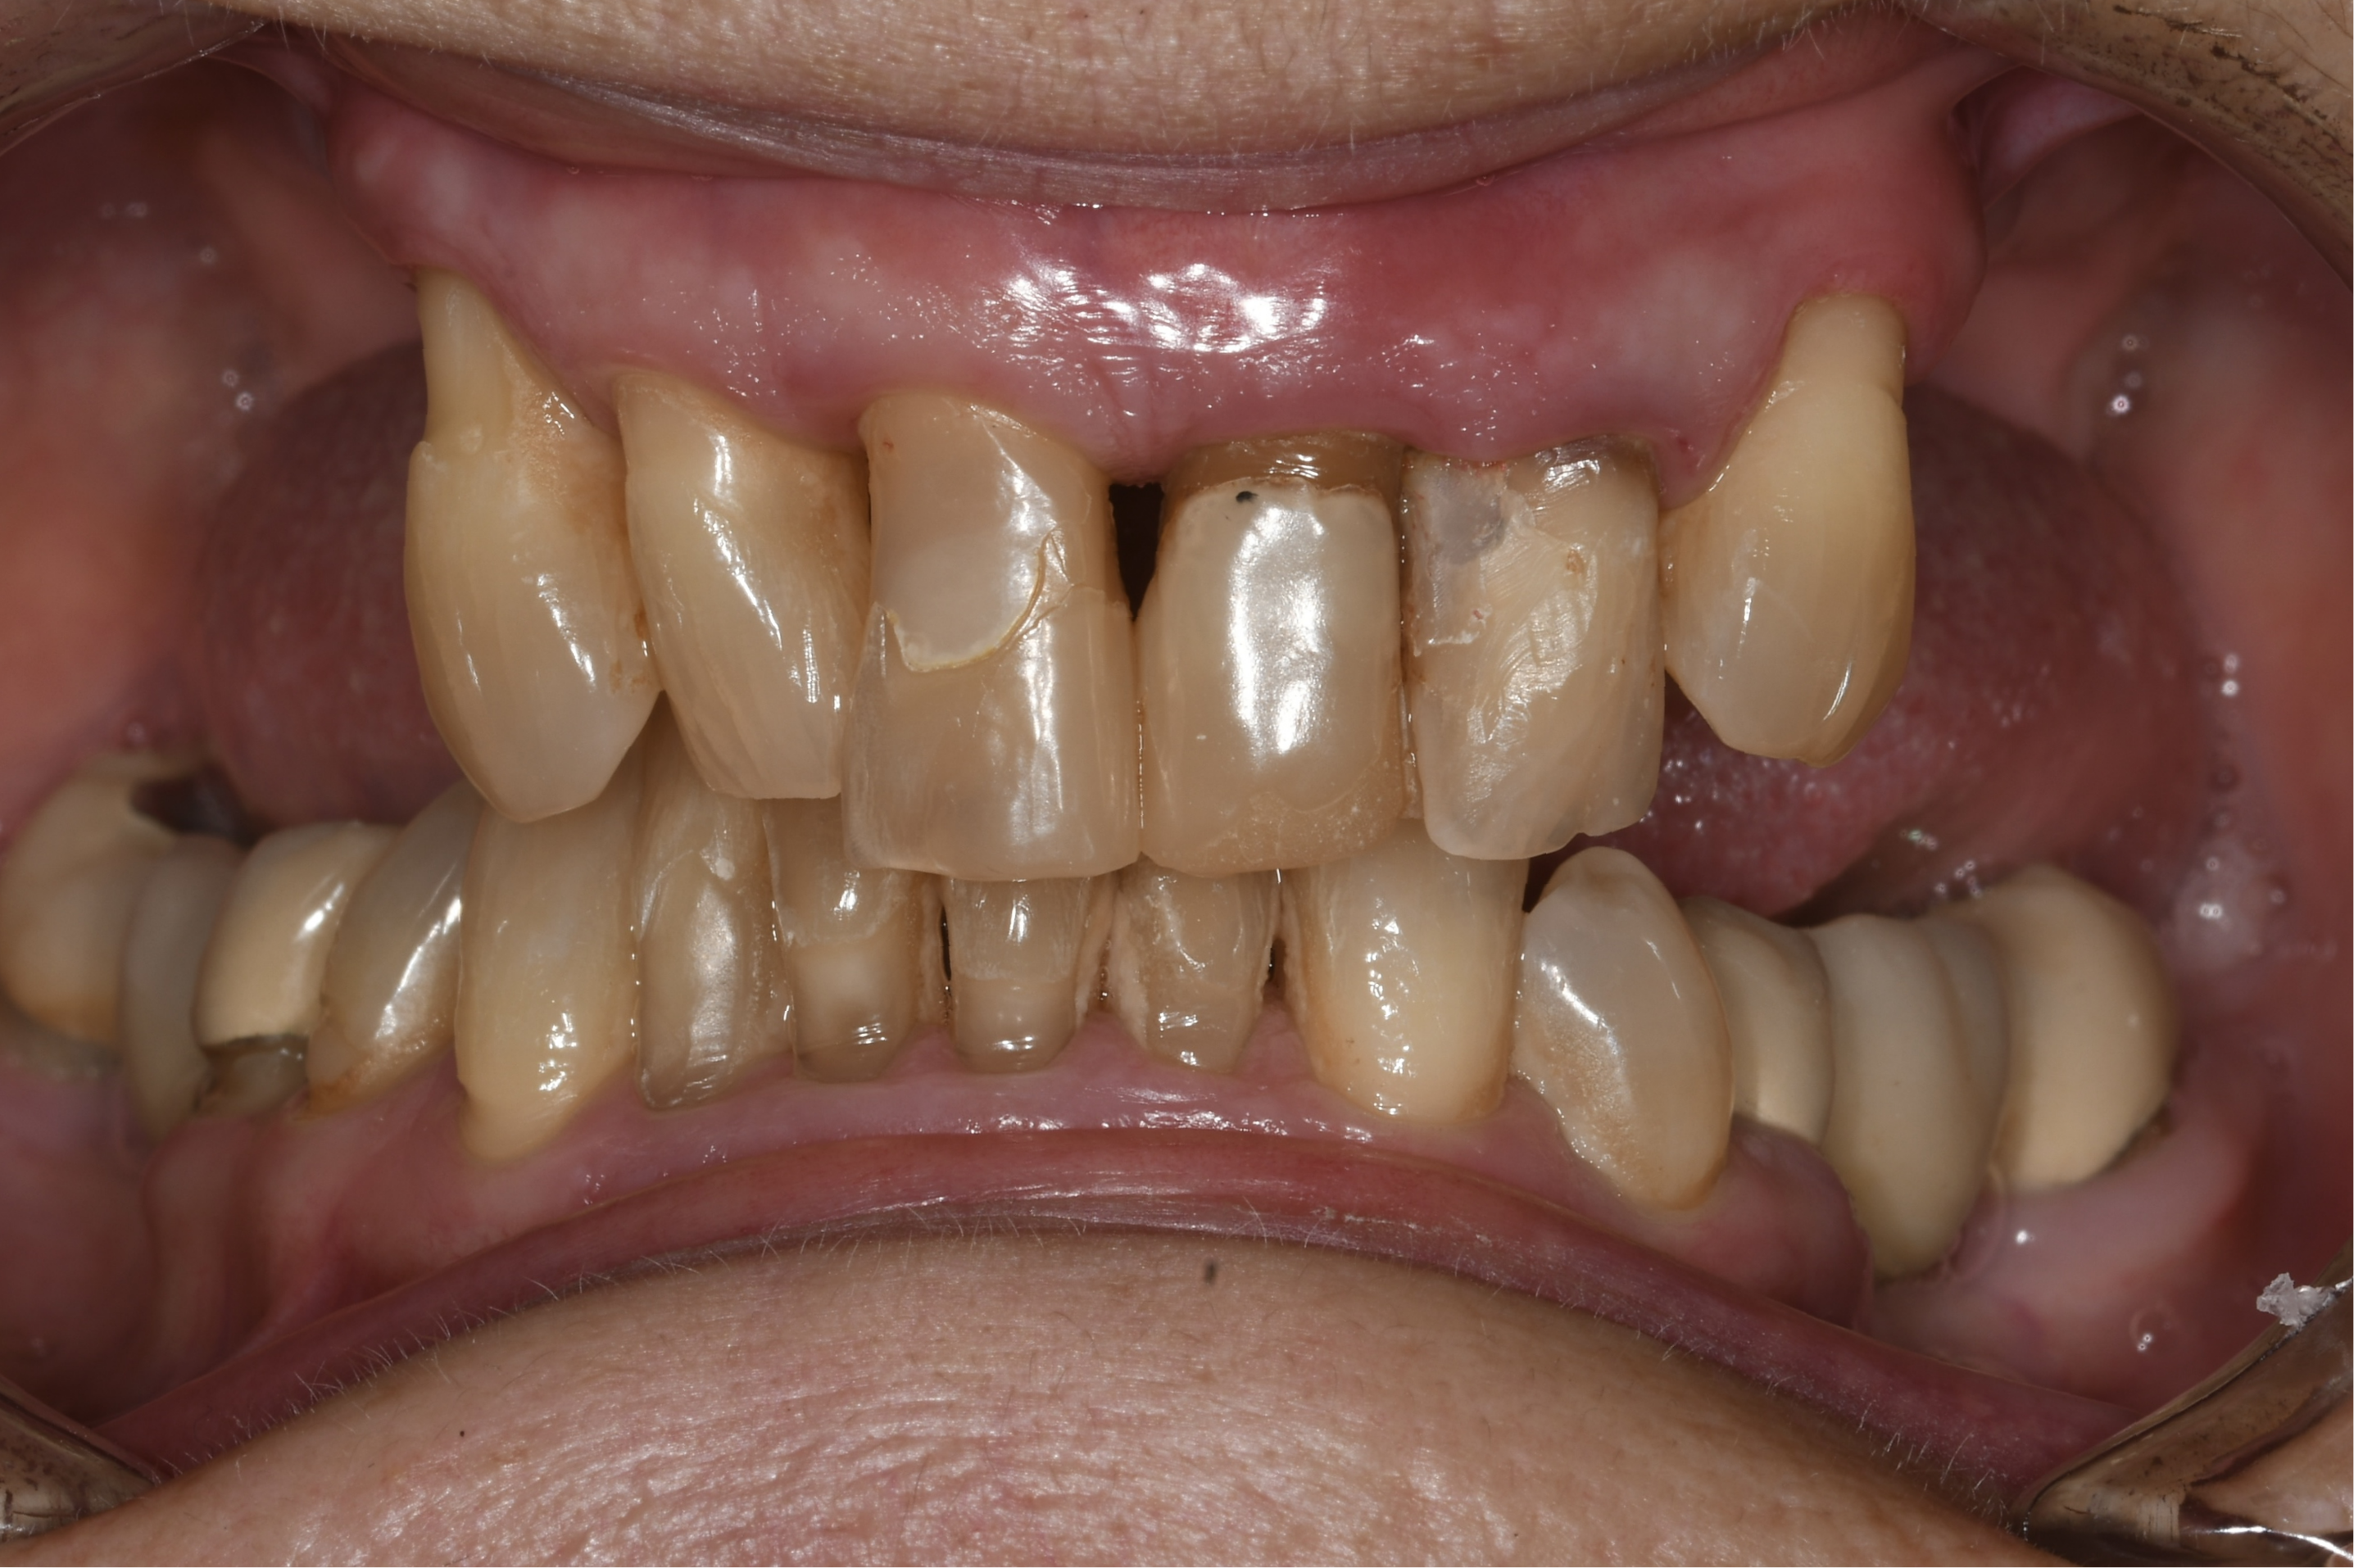

A 67-year-old female patient presented with a severely compromised anterior maxilla. Remaining teeth 13–23 showed advanced bone loss, periodontal breakdown, and a deep bite. The teeth were deemed non-restorable. The patient experienced functional limitations and significant aesthetic concern. Medical history was unremarkable.

Initial diagnostics included CBCT imaging and full-arch intraoral scanning. A digital wax-up with an increased vertical dimension of approximately 2 mm was created to simulate functional and aesthetic improvements. Fully digital implant planning was carried out, and a SMOP tooth supported guide was designed, anchored in the region of the lateral incisors.